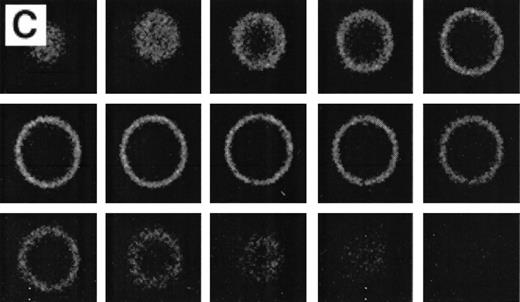

When normal RBC phospholipid asymmetry is scrambled by treatment with NEM, calcium, and ionophore they can be analyzed by fluorescent microscopy (Fig3A, B). Analysis by CSOM shows uniform labeling of the membrane by AV-FITC (Fig 3C) of these spherocytic cells. Because a simple wash in calcium-poor buffer removes all AV-FITC labeling from the cell, the data indicate that the AV-FITC complex is bound to PS on the outside of these cells, as was reported before.15

Analysis of RBCs incubated with FITC-labeled AV after treatment with calcium in the presence of 4 μmol/L ionophore A23187 by fluorescence microscopy. (A) A representative field of this population as observed in bright field and (B) in fluorescence; note the RBC ghost indicated by arrow. (C) A calcium ionophore scrambled spherocytic red cell analyzed by serial optical sections in confocal fluorescent microscopy.

Because the number of positive cells in the thalassemic RBC samples was low, the population was enriched in AV-FITC–positive cells by magnetic bead separation as described before.15 After separation, the cells were washed with calcium-free buffer, which removed all of the AV-FITC/magnetic bead complex from the cells. These RBCs were reincubated in AV-FITC in the presence of calcium to visualize the distribution of PS on the membrane surface. These unfixed AV-FITC–labeled RBCs were then studied by CSOM, and optical sections taken at 0.5 μm cuts were made when indicated (Fig 4). When it was necessary to simultaneously analyze the distribution of PS on the red cell surface and α-globin deposits on the cytosolic site of the membrane, AV-FITC–labeled cells were lightly fixed, permeabilized, and incubated with the murine monoclonal anti–α-globin antibody, followed by Texas-Red–labeled goat antimurine immunoglobulin antibody.17 18

Figure 4 shows representative fields of RBCs from a splenectomized patient with HbE/β-thalassemia PS exposing RBCs, enriched by magnetic bead separation, relabeled with AV-FITC, and analyzed by CSOM, showed two patterns of fluorescence. Approximately half of the AV-FITC–labeled thalassemic RBCs show a smooth rim fluorescence over the entire membrane (Fig 4A), similar to normal cells with a scrambled membrane (Fig 3). However, in other RBCs the AV-FITC membrane fluorescence was more heterogeneously distributed. In addition to a rim fluorescence, sites with increased fluorescence were observed, indicating that PS was enriched in these areas (Fig 4B). Interestingly, these AV-FITC–labeled sites at the surface of the cell were localized to areas that seemed to bulge over an inclusion body as shown in the equatorial cut of such labeled cells shown in Fig 4B. Because this patient had severe β-thalassemia intermedia, it was logical to suppose that the inclusion was a membrane associated deposit of excess α-globin chains, which we tried to confirm using the monoclonal antibody to denatured α-globin chains shown by Texas-Red–labeled antimurine immunoglobulin.

The equatorial cut (midsection) of such labeled cells showed the enrichment of Texas Red in distinct areas, indicating that denatured α-globin chains were localized in domains adjacent to the membrane, confirming results reported before.18 When such RBCs were analyzed for both AV-FITC (green) and anti–α-globin/Texas-Red (red), fluorescence microscopy showed a bright-yellow fluorescence in dual-color analysis, indicating that both AV-FITC and the Texas-Red label were enriched in the same membrane regions (Fig 4B and C). In contrast, the cells that labeled homogeneously with AV-FITC did not label with Texas Red. These data strongly suggest a colocalization of denatured α-globin chains and PS in the same area.

The labeling with AV-FITC allows identification of individual cells that expose PS by fluorescent microscopy. AV-FITC binds to the outer surface of cells that have lost their normal phospholipid asymmetry as indicated by CSOM analysis. Those cells that have lost their membrane integrity (ghosts) are brightly labeled due to the fact that AV-FITC has access to the PS in the inner monolayer. AV-FITC can be removed from intact red cells by a simple wash in calcium-poor buffer, a further indication that the FITC-labeled 38 kD protein has only access to the outer surface of the cell. In order to increase the number of AV-FITC–positive cells in the thalassemic red cell population to make analysis by fluorescent microscopy more feasible, we used a technique that selects these cells by magnetic bead separation.15Analysis after renewed labeling of unfixed RBC with AV-FITC shows at least two types of PS exposure in thalassemic red cells. On the one hand, a similar labeling is found (Fig 4A) as with normal red cells scrambled with calcium and ionophore as shown in Fig 3C. In these cells, uniform rim fluorescence indicates a uniform distribution of PS on the outer surface. Other cells showed enhanced domains of PS on the surface of the thalassemic red cells (Fig 4B). The underlying mechanism for these hot spots is not clear. These data suggest that the normal maintained asymmetry of the PL bilayer can be disrupted locally. However, based on the rapid diffusion rates of phospholipids in the plane of the bilayer before AV-FITC labeling, one would not expect these domains in the case of unrestricted movement of PS on the surface of the cell. Hence, this would lead to the conclusion that PS movement is restricted in the plane of the bilayer of these cells confining PS to local areas that are identified by AV-FITC labeling. Although the concept of lipid domains as the result of restricted movement has been hypothesized, few reports have been able to indicate such regions.